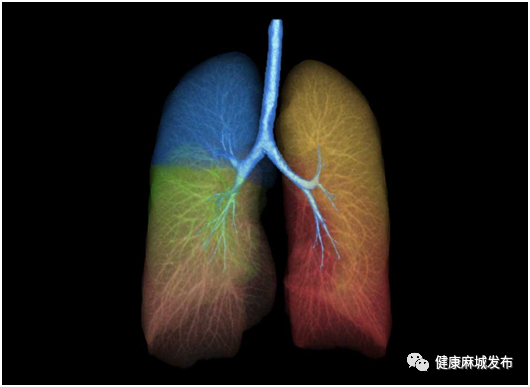

肺气肿分析:提供了肺气肿含量的测量工具,直观显示肺气肿的扩散情况,包括左右肺的自动分割及编辑、肺密度分析及参数计算等功能。